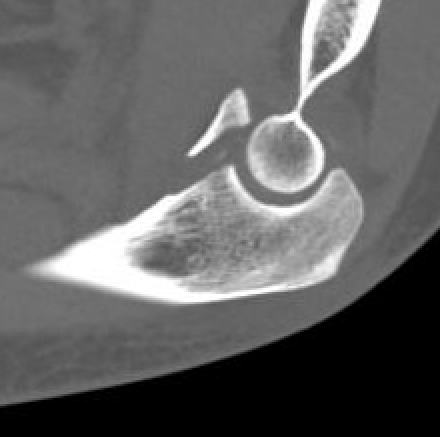

Universal posterior approach with radial head replacement and medial approach with medial buttress plate

coroncorocoronoid